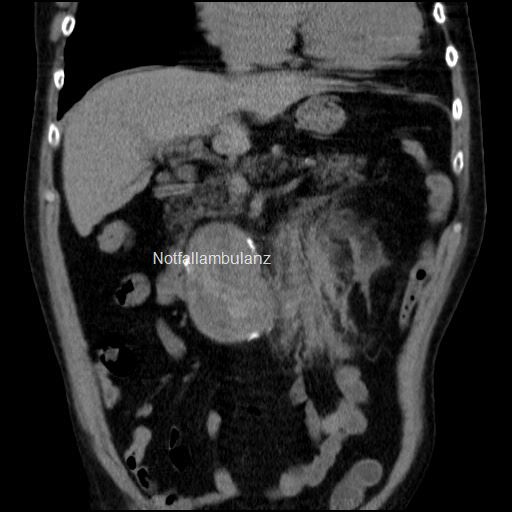

Fall 82: Der akute Bauchschmerz

Ein 84-jähriger Bewohner eines Altenheimes wird mit dem Rettungsdienst vorgestellt. Er klagt über akut eingesetzte abdominelle Beschwerden ohne Übelkeit oder Erbrechen. Diese bestünden bereits seit 2 Stunden und hätten nicht auf Gabe von Analgetika angesprochen.

Bei dem Patienten ist ein Diabetes mellitus Typ II bekannt sowie eine KHK, Hypertonie und eine Niereninsuffizienz. Es wird u.a. ASS eingenommen.

Körperliche Untersuchung:

84-jähriger schlanker Mann in reduziertem Allgemein- und Ernährungszustand. Die Bauchdecken sind weich und ohne Abwehrspannung. Im Unterbauch tastet sich eine Resistenz, die nicht als druckdolent angegeben wird. Die Peristaltik ist reduziert, jedoch nicht klingend. Keine Beinödeme. Fußpulse nur schwach tastbar.

Befunde:

Sonografisch sind die Oberbauchorgane unauffällig. Keine freie Flüssigkeit in den Pouches. Die Aorta jedoch ist oberhalb der Bifurkation auf 8 cm erweitert.

Es besteht der Verdacht eines  symptomatischen Aortenaneurysmas. Es wird ein erweitertes Labor mit der Anforderung von 4 Blutkonserven. Ein Angio-CT schließt sich an und zeigt folgenden Befund.

Diagnose:

Gedeckt perforiertes Aortenaneurysma